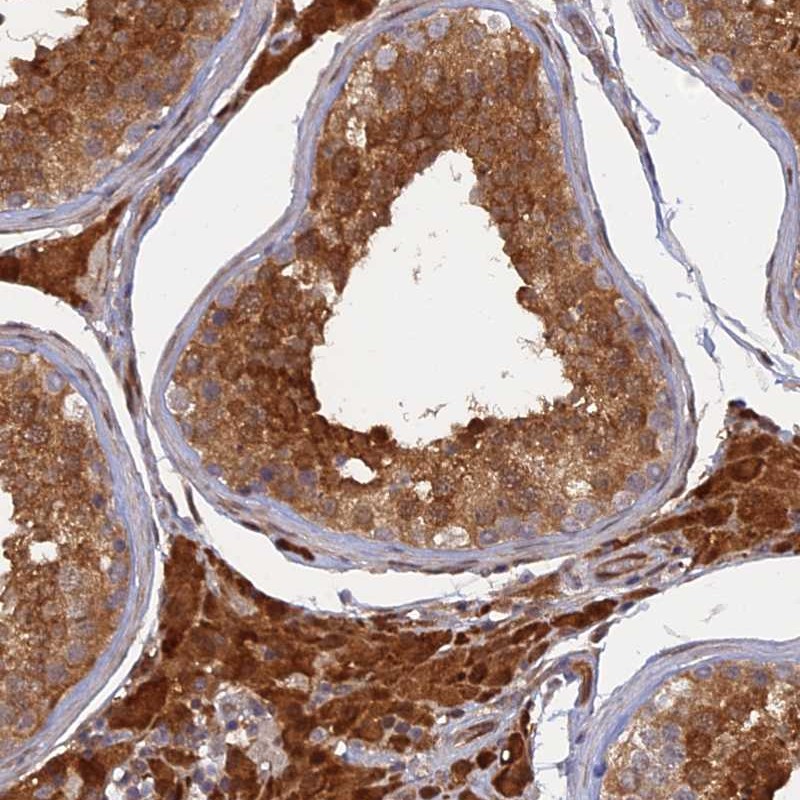

Immunohistochemical staining of human testis shows strong cytoplasmic and nuclear positivity in cells in seminiferus tubules and Leydig cells.